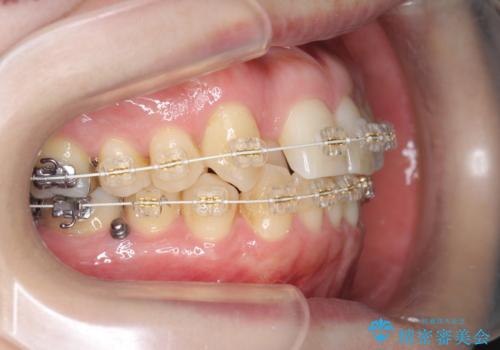

- 審美装置

- 2年3ヶ月

矯正用のミニスクリューを使用し、また、前歯をIPRすることで正中の左へのずれを最小限に抑えています。

上の前歯が内側に入っているクロスバイトは、笑った時に影になってしまい、かなり目立ちます。

内側に入っている前歯を外に出すだけで劇的に印象が変わります。